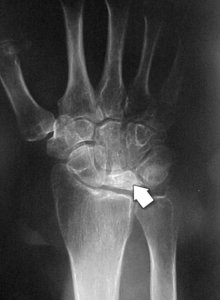

During the first stage of the disease, the symptoms are similar to those of a wrist sprain. Although the blood supply to the lunate has been disrupted, x-rays may still appear normal or suggest a possible fracture. An MRI scan can better detect blood flow and is helpful in making the diagnosis in this early stage.

Stage 1. (Left) This illustration shows a fracture of the lunate during the early phase of the disease.(Right) An x-ray of a patient's wrist during Stage I shows no deterioration of the lunate bone.

Reproduced and adapted with permission from Allan CH, Joshi A, Lichtman DM: Kienböck's disease: diagnosis and treatment. J Am Acad Orthop Surg 2001; 9 : 128-136.